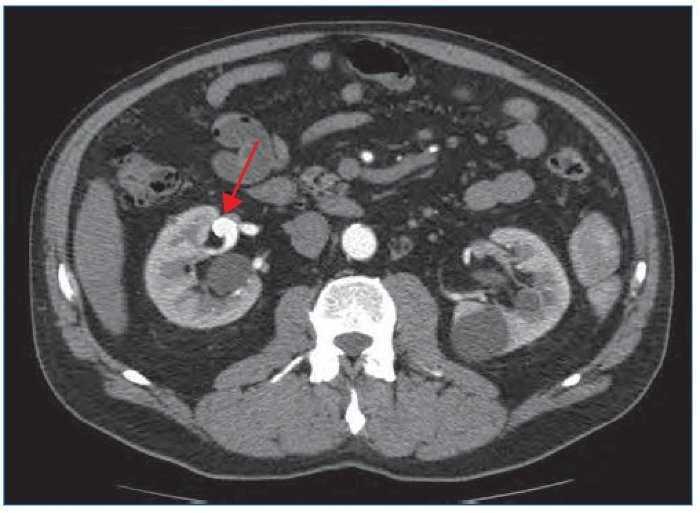

Se realiza arteriografía con sustracción digital intraarterial, que confirma el aneurisma en la rama inferior de la bifurcación posterior de la arteria renal derecha de 11,4 × 15,8 mm de diámetro (figura 2).

Figura 2. Arteriografía que confirma el aneurisma en la rama inferior de la bifurcación posterior de la arteria renal derecha.